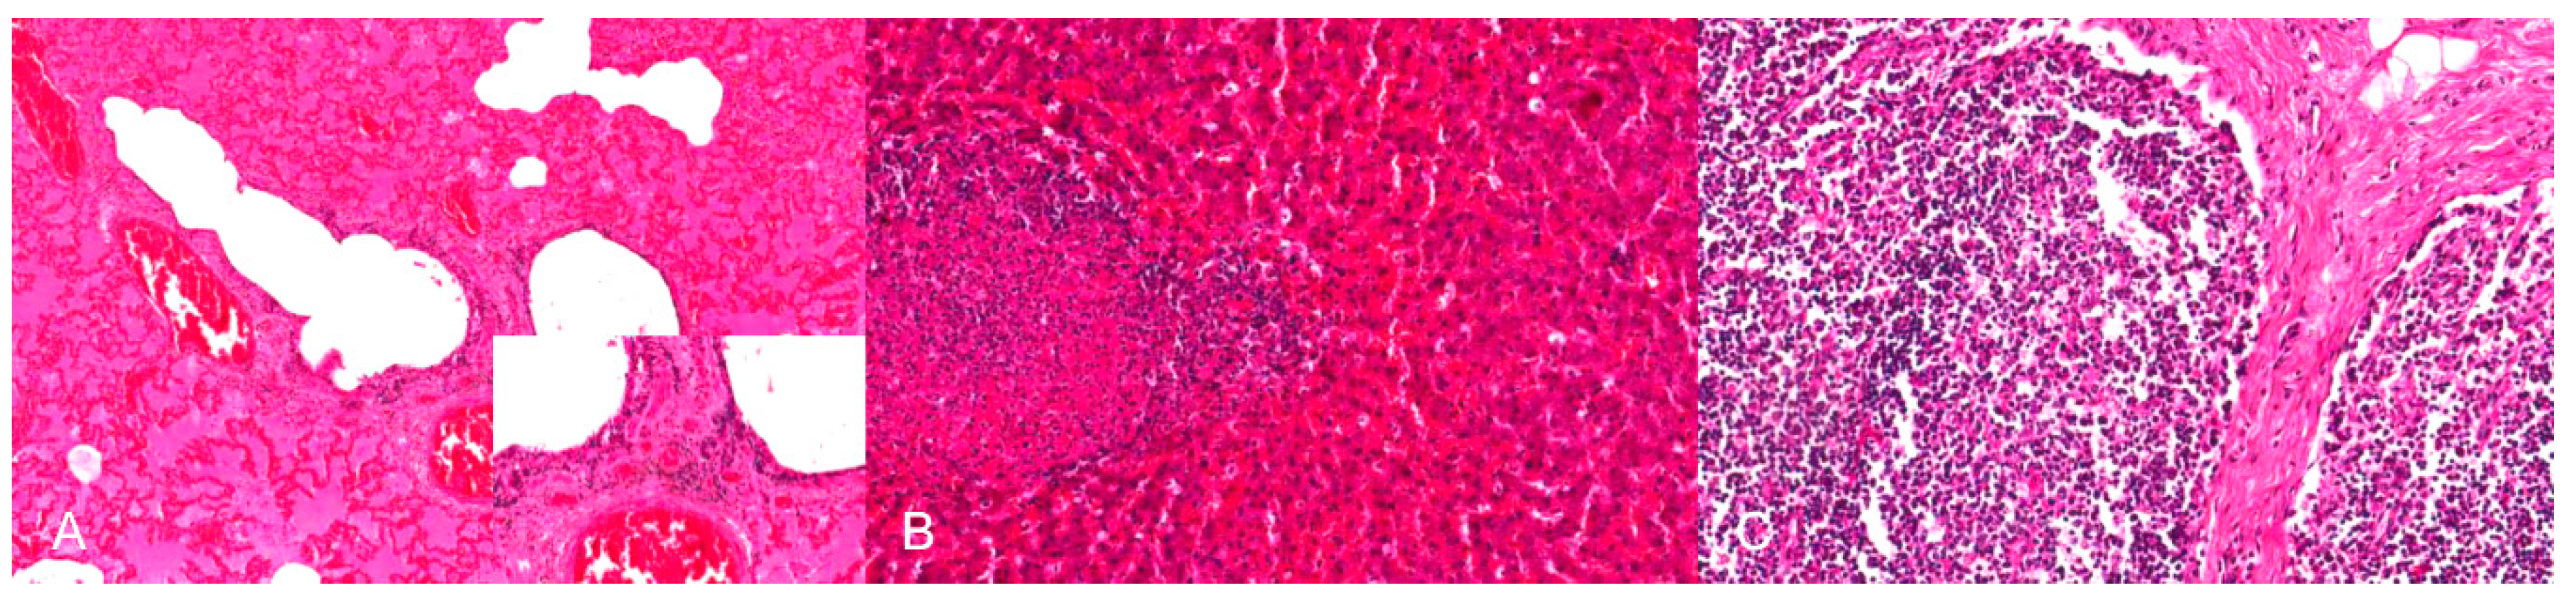

4.4.4. Histopathology

By immunohistochemistry, PRV antigen is mainly present in neurons and glial cells of the brainstem, trigeminal ganglia, spinal cord and abdominal vegetative plexus such as the myenteric plexus [75,76,85,87] (Figure 6). Further, cardiomyocytes as well as fibrocytes and glandular epithelium of the stomach carry PRV antigens [76]. This corresponds to observations in a cat showing antigen positive cells in the intestinal tract and in sympathetic lumbar ganglia [84]. In experimentally inoculated dogs antigen is also present in the pancreas and parotid gland [93], and in the sympathetic stellate, celiac and caudal mesenteric ganglia [78]. Mild to severe nonsuppurative encephalitis mainly affects the brainstem [28,75,76,78,81,84,85,86,87] (Figure 7). Inflammation of the cerebrum [85,88], midbrain and cerebellum [28] may also occur. The inflammatory response is characterized by neuronal necrosis of brain parenchyma and perivascular cuffs consisting of mainly lymphocytes and macrophages. There is glial cell proliferation in the grey and white matter, satellitosis, neuronophagia and more or less intralesional eosinophilic intranuclear inclusion bodies. The adjacent meninges are infiltrated by mononuclear cells, and endothelial cells can be hypertrophic [86]. Inflammatory infiltrates are further detectable in trigeminal ganglia, spinal cord, abdominal ganglia and vegetative plexus as well as in the adrenal gland [75,80,82,84,85] (Figure 8). The heart, lung, kidney, liver, intestinal tract, tonsil are also affected by inflammation, necrosis or hemorrhage [78,81,84,86] (Figure 9). Degeneration and necrosis of cardiomyocytes with mild or no inflammatory reaction can occur in dogs. Focal necrotic areas are evident in the liver, whereas lymphoid depletion as well as hemorrhages are seen in the thymus and lymph nodes (Figure 9). Especially in cats, tonsillary necrosis of the crypt epithelium is reported [84,92]. In scratched skin regions necro-ulcerative dermatitis with subcutaneous edema are present [75,78].

Figure 9.

Inflammation and necrosis in different organs in a PRV-infected dog. (A) Mild lymphocytic bronchiolitis with severe, diffuse alveolar edema. (B) Focal hemorrhagic necrosis in the liver. (C) Multifocal necrosis of lymphocytes in the lymph node resulting in lymphoid depletion, H.E. (Courtesy: Institute for Veterinary Disease Control, Mödling).